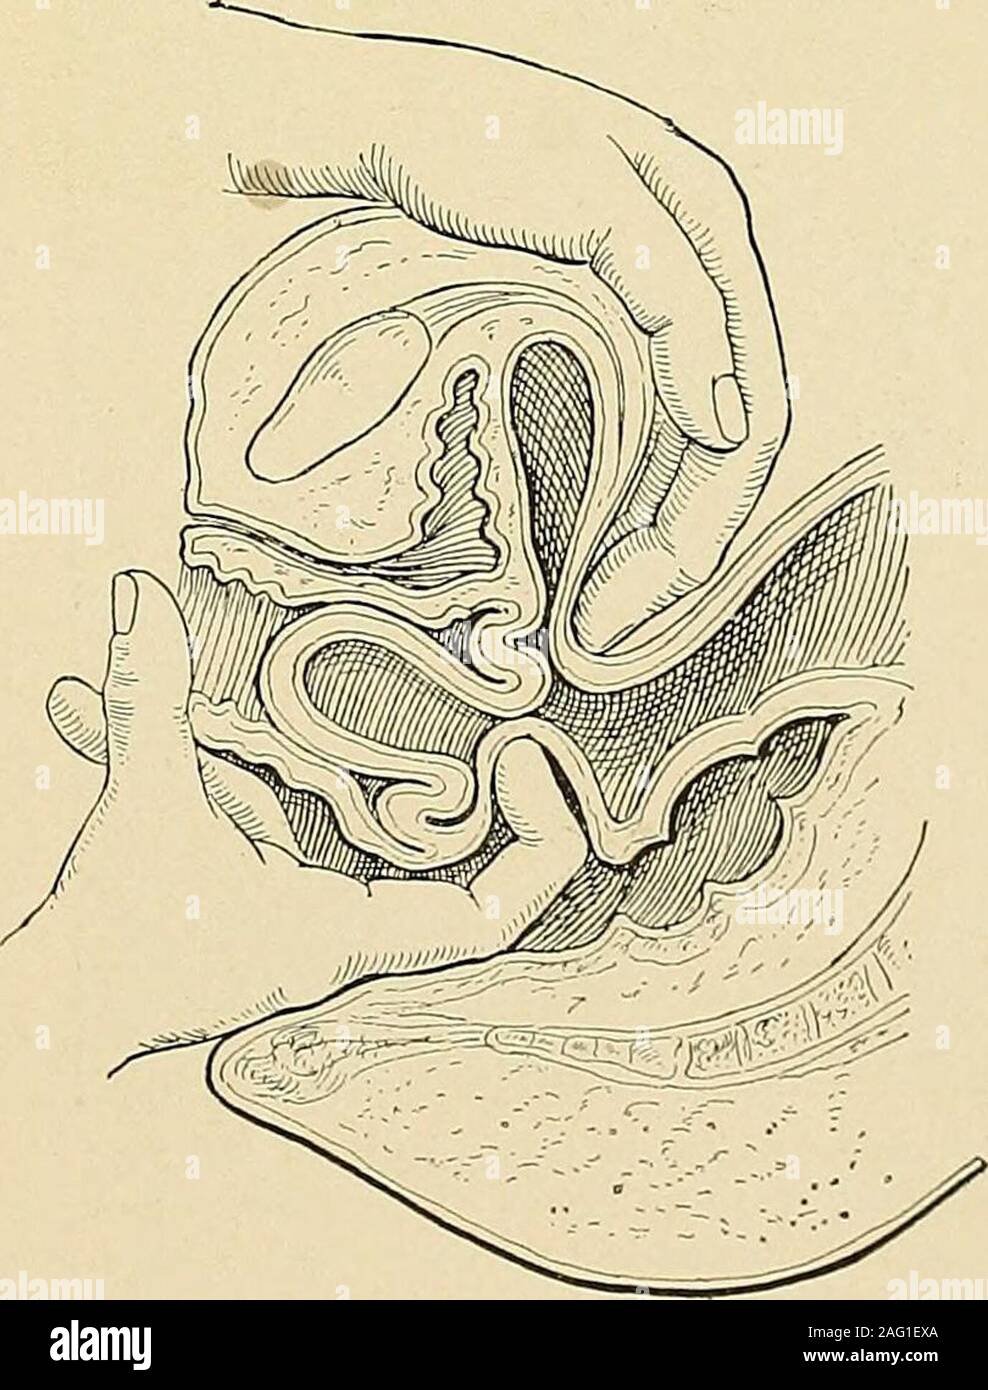

ANILLO VAGINAL CENTRO CL NICO BETANZOS 60 M dicos en Madrid on sale, Anticonceptivos Centro ginecologia Oviedo on sale, Anillo vaginal qu es ventajas inconvenientes y gu a de uso on sale, Anillo anticonceptivo qu es s ntomas y tratamiento Top Doctors on sale, Nuvaring anillo vaginal el anticonceptivo sin olvidos on sale, NuvaRing Anillo Vaginal Guadalajara Ginecolog a en Guadalajara on sale, Anillo Anticonceptivo M todo Hormonal on sale, Pesario anillo grueso Dr. Arabin para tratamiento de prolapso uterino on sale, Lanzan un nuevo anticonceptivo hormonal que se coloca en la vagina on sale, El anillo vaginal es un anticonceptivo Dr. Mao Yin Soto on sale, Anillo vaginal qu es ventajas inconvenientes y gu a de uso on sale, Anillo de retractor ginecol gico de un solo uso r01 n 8 ganchos on sale, Amazon KH66ZKY Modelo de ense anza de maniqu Modelo on sale, Lanzan un nuevo anticonceptivo hormonal que se coloca en la vagina on sale, Simulador ginecol gico para m todos anticonceptivos More Than on sale, Anillo Vaginal Anticonceptivo en Guadalajara Cl nica para la on sale, GineForum Granada on sale, Dispositivo Intrauterino de extracci n de anillo pinzas de on sale, KH66ZKY Modelo de Examen ginecol gico Modelo Uterino Anillo on sale, Los s ntomas tempranos del c ncer de ovario as comienza el tumor on sale, Margutta Anillo Gea Farmaten on sale, Se aprob un nuevo anticonceptivo femenino un anillo vaginal on sale, Pesario anillo Dr. Arabin para tratamiento de prolapso uterino on sale, Anillos Vaginales Anticonceptivos Ginemedic on sale, El anillo vaginal anticonceptivo y sus efectos secundarios on sale, Margutta Anillo Tedi Farmaten on sale, Maniqu Femenino Modelo de Examen ginecol gico Anillo uterino on sale, L ser ginecol gico en Salamanca Cl nica Menc a on sale, Todo lo que debes saber sobre el Anillo Vaginal on sale, Pesario Ginecologico De Silicona MercadoLibre on sale, C mo se usa el anillo vaginal Planned Parenthood on sale, Diagn stico ginecol gico . y contienen epipl n intestino O on sale, Pesario Uterino Anillo con refuerzo soporte SUMSA on sale, Anillo uterino ginecol gico del Dr. Schneiderman urpsch2.0 on sale, C mo se usa el anillo vaginal Planned Parenthood on sale, Dolor en los Pechos Instituto Ginecol gico Dra. G mez Roig on sale, FIORIBELLA ANILLO VAGINAL CAJA X 1 UNID on sale, Instituto Ginecol gico PR Si utilizas anticonceptivos como la on sale, Velastisa Intim Lubricante hidrogel Duplo Anillo Farmacia Jim nez on sale, Sonda uterina para la extracci n de los ganchos de anillo para la on sale, Anillo anticonceptivo para Adolescentes Nemours KidsHealth on sale, Simulador ginecol gico para m todos anticonceptivos More Than on sale, Blog sobre fertilidad y ginecolog a. Cl nica Medrano on sale, Simulador Ginecol gico para la Educaci n del Paciente Medical on sale, El diagn stico y tratamiento de enfermedades de la mujer. Fig. 322 on sale, Sabes c mo se usa el anillo vaginal El anillo es muy on sale, Lotus Dra. Jennifer del Valle M todos anticonceptivos hormonales on sale, P gina 71 Im genes de Chequeo Ginecologico Descarga gratuita on sale, Anillo vaginal Wikipedia la enciclopedia libre on sale, t ndem intrauterino colpostatos ovoides anillos o cilindros on sale.

Anillo ginecologico on sale